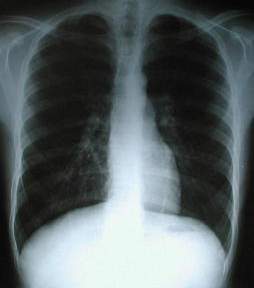

Radiología del Tórax

En la radiología preoperatoria posteroanterior PA, (abajo a la Izquierda), apreciamos la imagen cardiaca centrada en el tórax con aplanamiento del diafragma y horizontalización de los arcos costales, el dibujo pulmonar normal.

Rx. Tórax PA